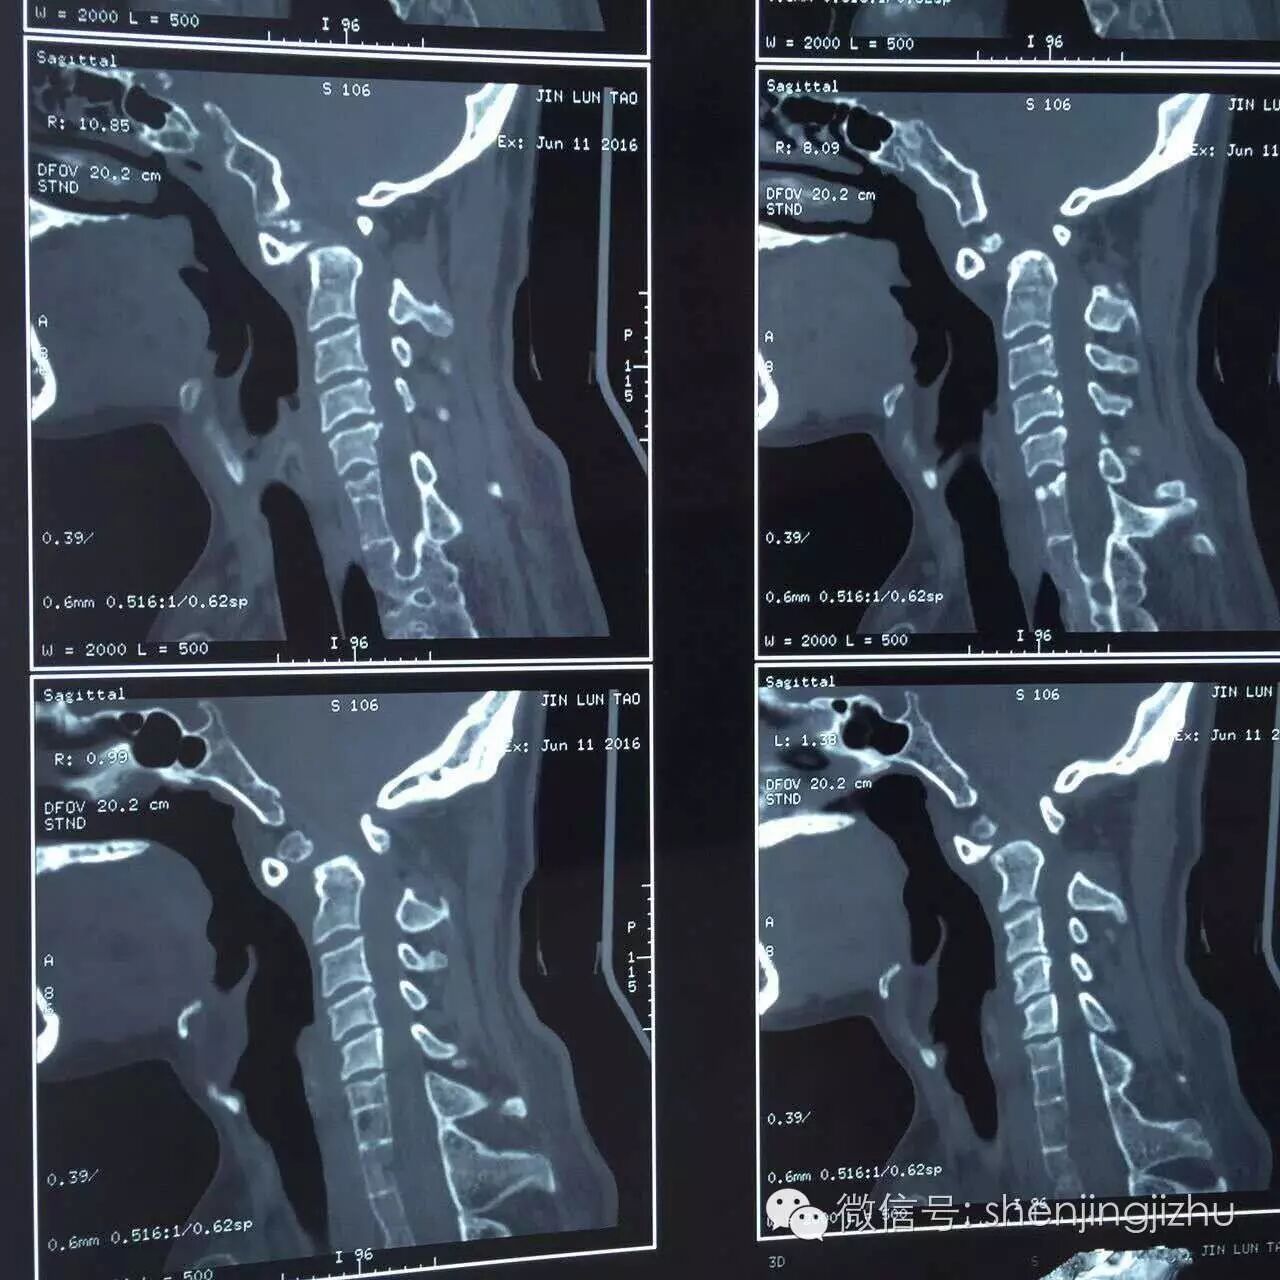

CT

术前诊断:颅颈畸形

先天性齿状突分离;

自发性寰枢关节半脱位;

颈0-2椎管狭窄